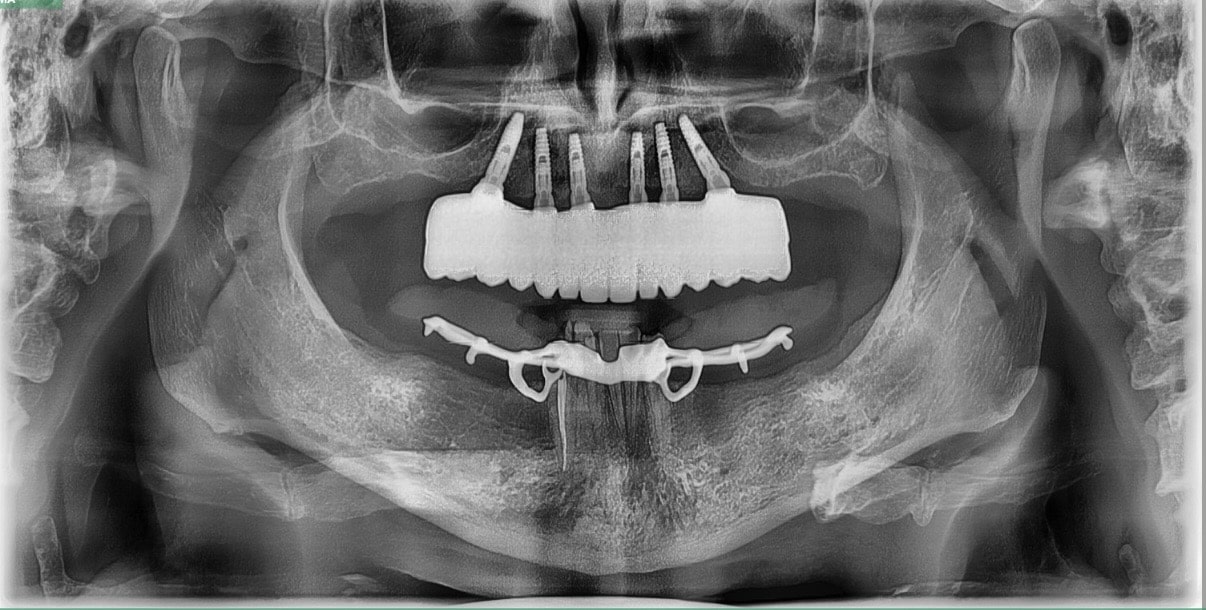

We knew that John was a good candidate for All-on-4 implants, so our team worked to design a bright, healthy smile for John. During our comprehensive examination, we took x-rays, surveyed the damage, and created an upper arch that restored the natural appearance of his teeth.